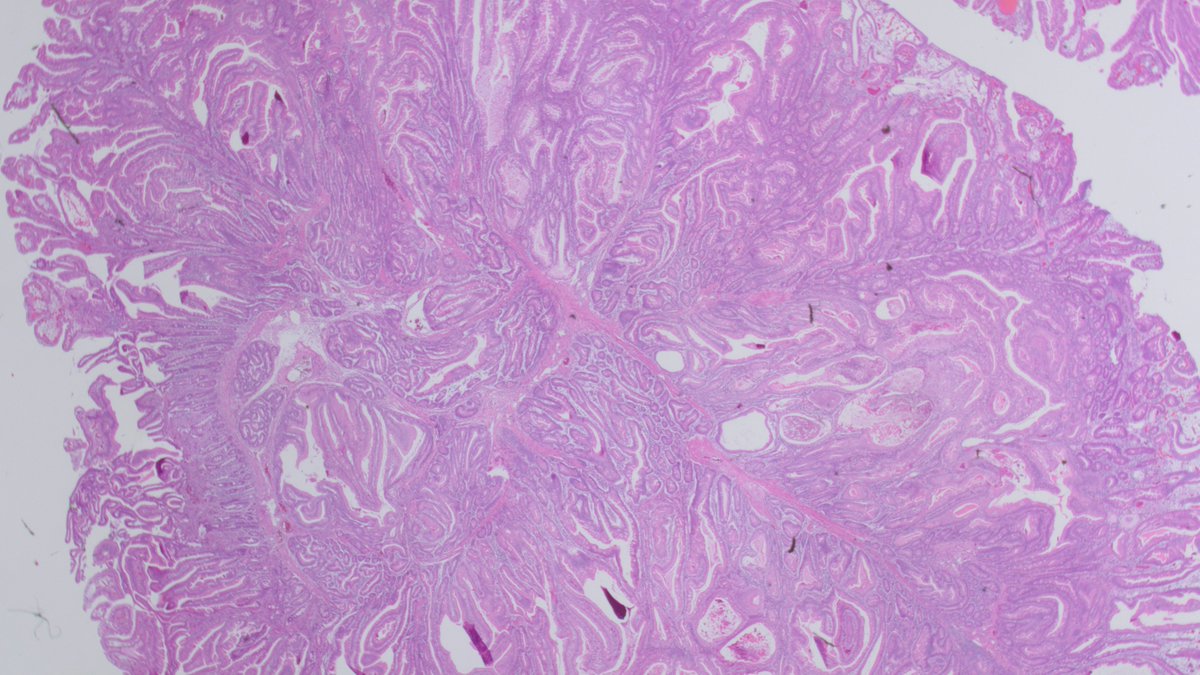

Hamartomatous Polyp, Peutz-Jeghers polyp, papillary architecture, arborizing/branching smooth muscle bundles, STK11 #GIpath #PathTwitter #pathology #Pathboards #GIPS #pathologists Florida Society of Pathologists CAPathologists ASCP #pathresidents